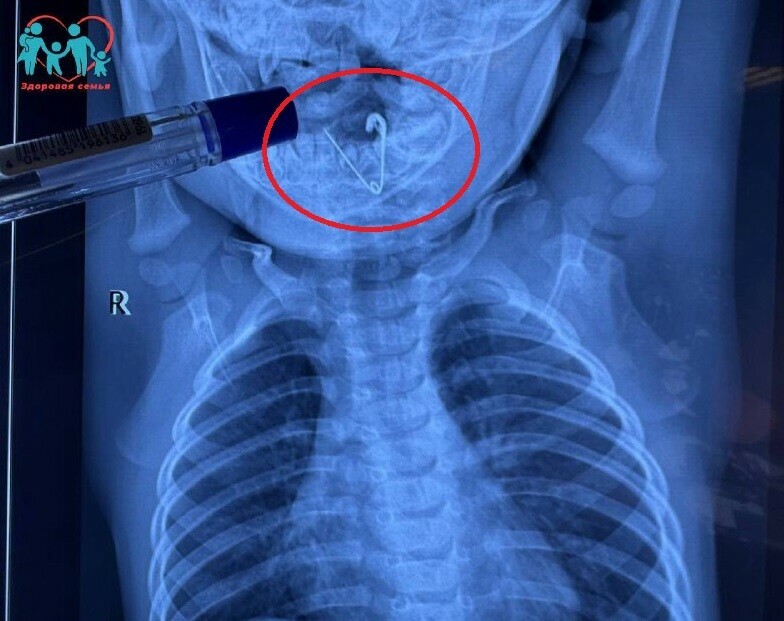

В больнице, куда экстренно госпитализировали младенца, сделали обзорную рентгенографию органов грудной клетки. В пищеводе была обнаружена тень инородного тела. На снимке была четко видна открытая булавка. Врачи удалили ее при помощи щипцов под контролем эндоскопической техники. Ребенок перенес операцию хорошо и вскоре его выпишут.